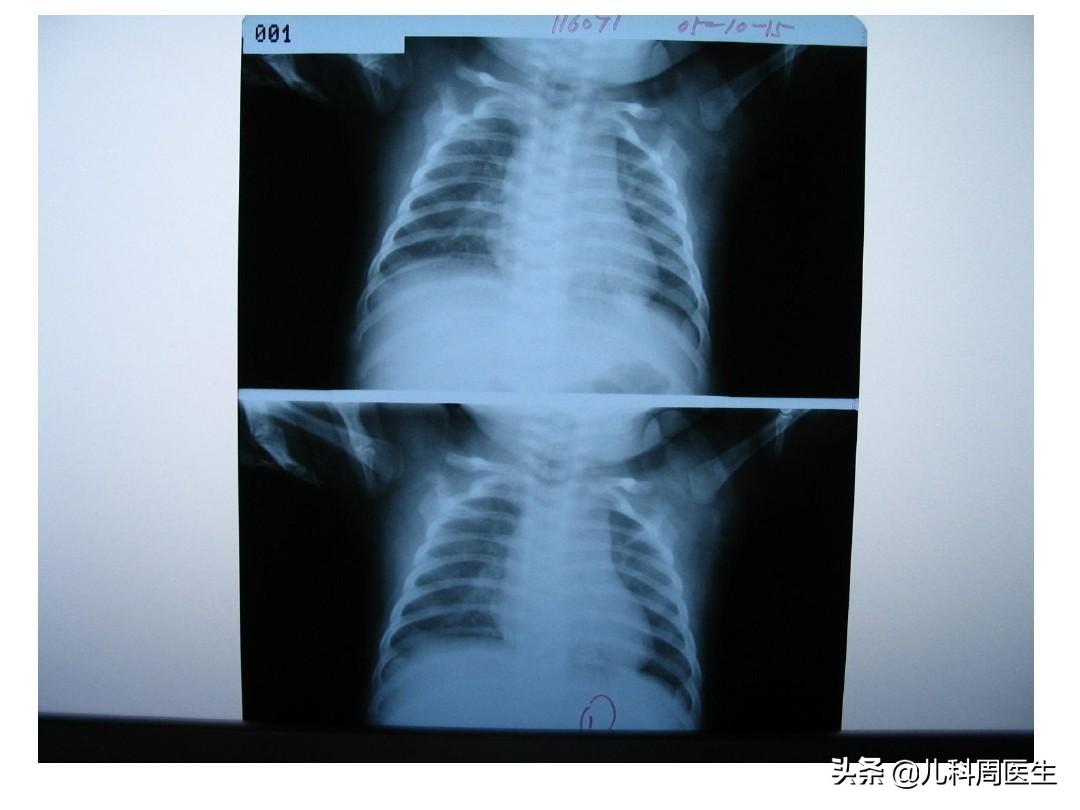

肺气肿、肺不张

X线胸片检查可显示: 肺部过度充气征(肺气肿)和斑片状阴影、及肺不张改变。这是诊断婴儿毛细支气管的重要方法和依据;相反,血常规正常,咽拭子可检出病原体。